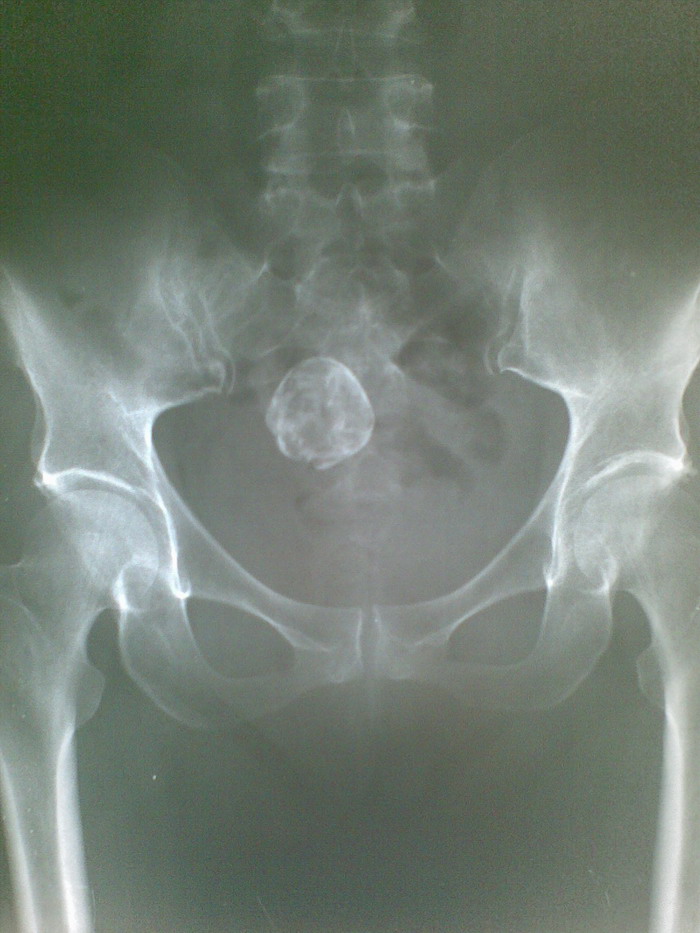

女 56岁 双侧膝关节疼痛半年.

左股骨下端骨岛可能性大,骨盆内椭圆形钙化影,内部密度欠均,畸胎瘤?腹腔其它钙化?建议平片侧位及ct检查。

1、盆腔畸胎瘤。

2、左股骨股梗死可能,骨岛、内生软骨瘤待排,建议mri检查。

1)左股骨下端骨岛可能性大。2)骨盆内椭圆形钙化影,边缘清楚,内部密度不均匀;不排除畸胎瘤可能。建议:行ct扫描检查。

骨梗死位于髓腔的中央,而这个病变位于髓腔皮质旁,我还是考虑内生软骨瘤。盆腔内类圆形钙化影我认为是畸胎瘤。

盆腔钙化多考虑子宫肌瘤钙化,左股骨下段骨梗死。